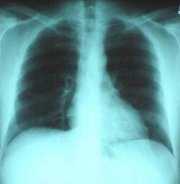

Normal Radiograph